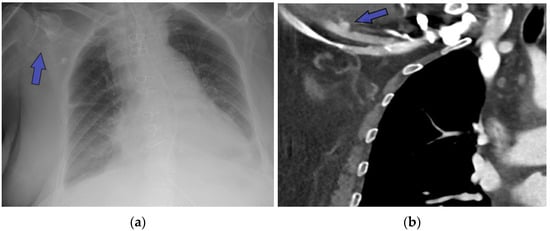

The proximity of the native ascending aorta or aortic graft to the sternum often necessitates the establishment of peripheral arterial access prior to redo sternotomy. Knowledge of previous access sites through the operation notes, clinical examination, and imaging is essential. While more technical details are presented in the section regarding specific surgical consideration in redo FET, presence of hemostatic clips (Figure 2a), vascular graft stumps (Figure 2b), or iatrogenic injuries such as arterial stenosis (Figure 2c) would inform the decision regarding access sites for safe peripheral cannulation.

Figure 2.

When establishment of peripheral arterial cannulation is considered, the use of imaging allows for identification hemostatic clips (a), vascular graft stumps (b), or iatrogenic injuries such as arterial stenosis (c) to identify the suitable remaining sites.